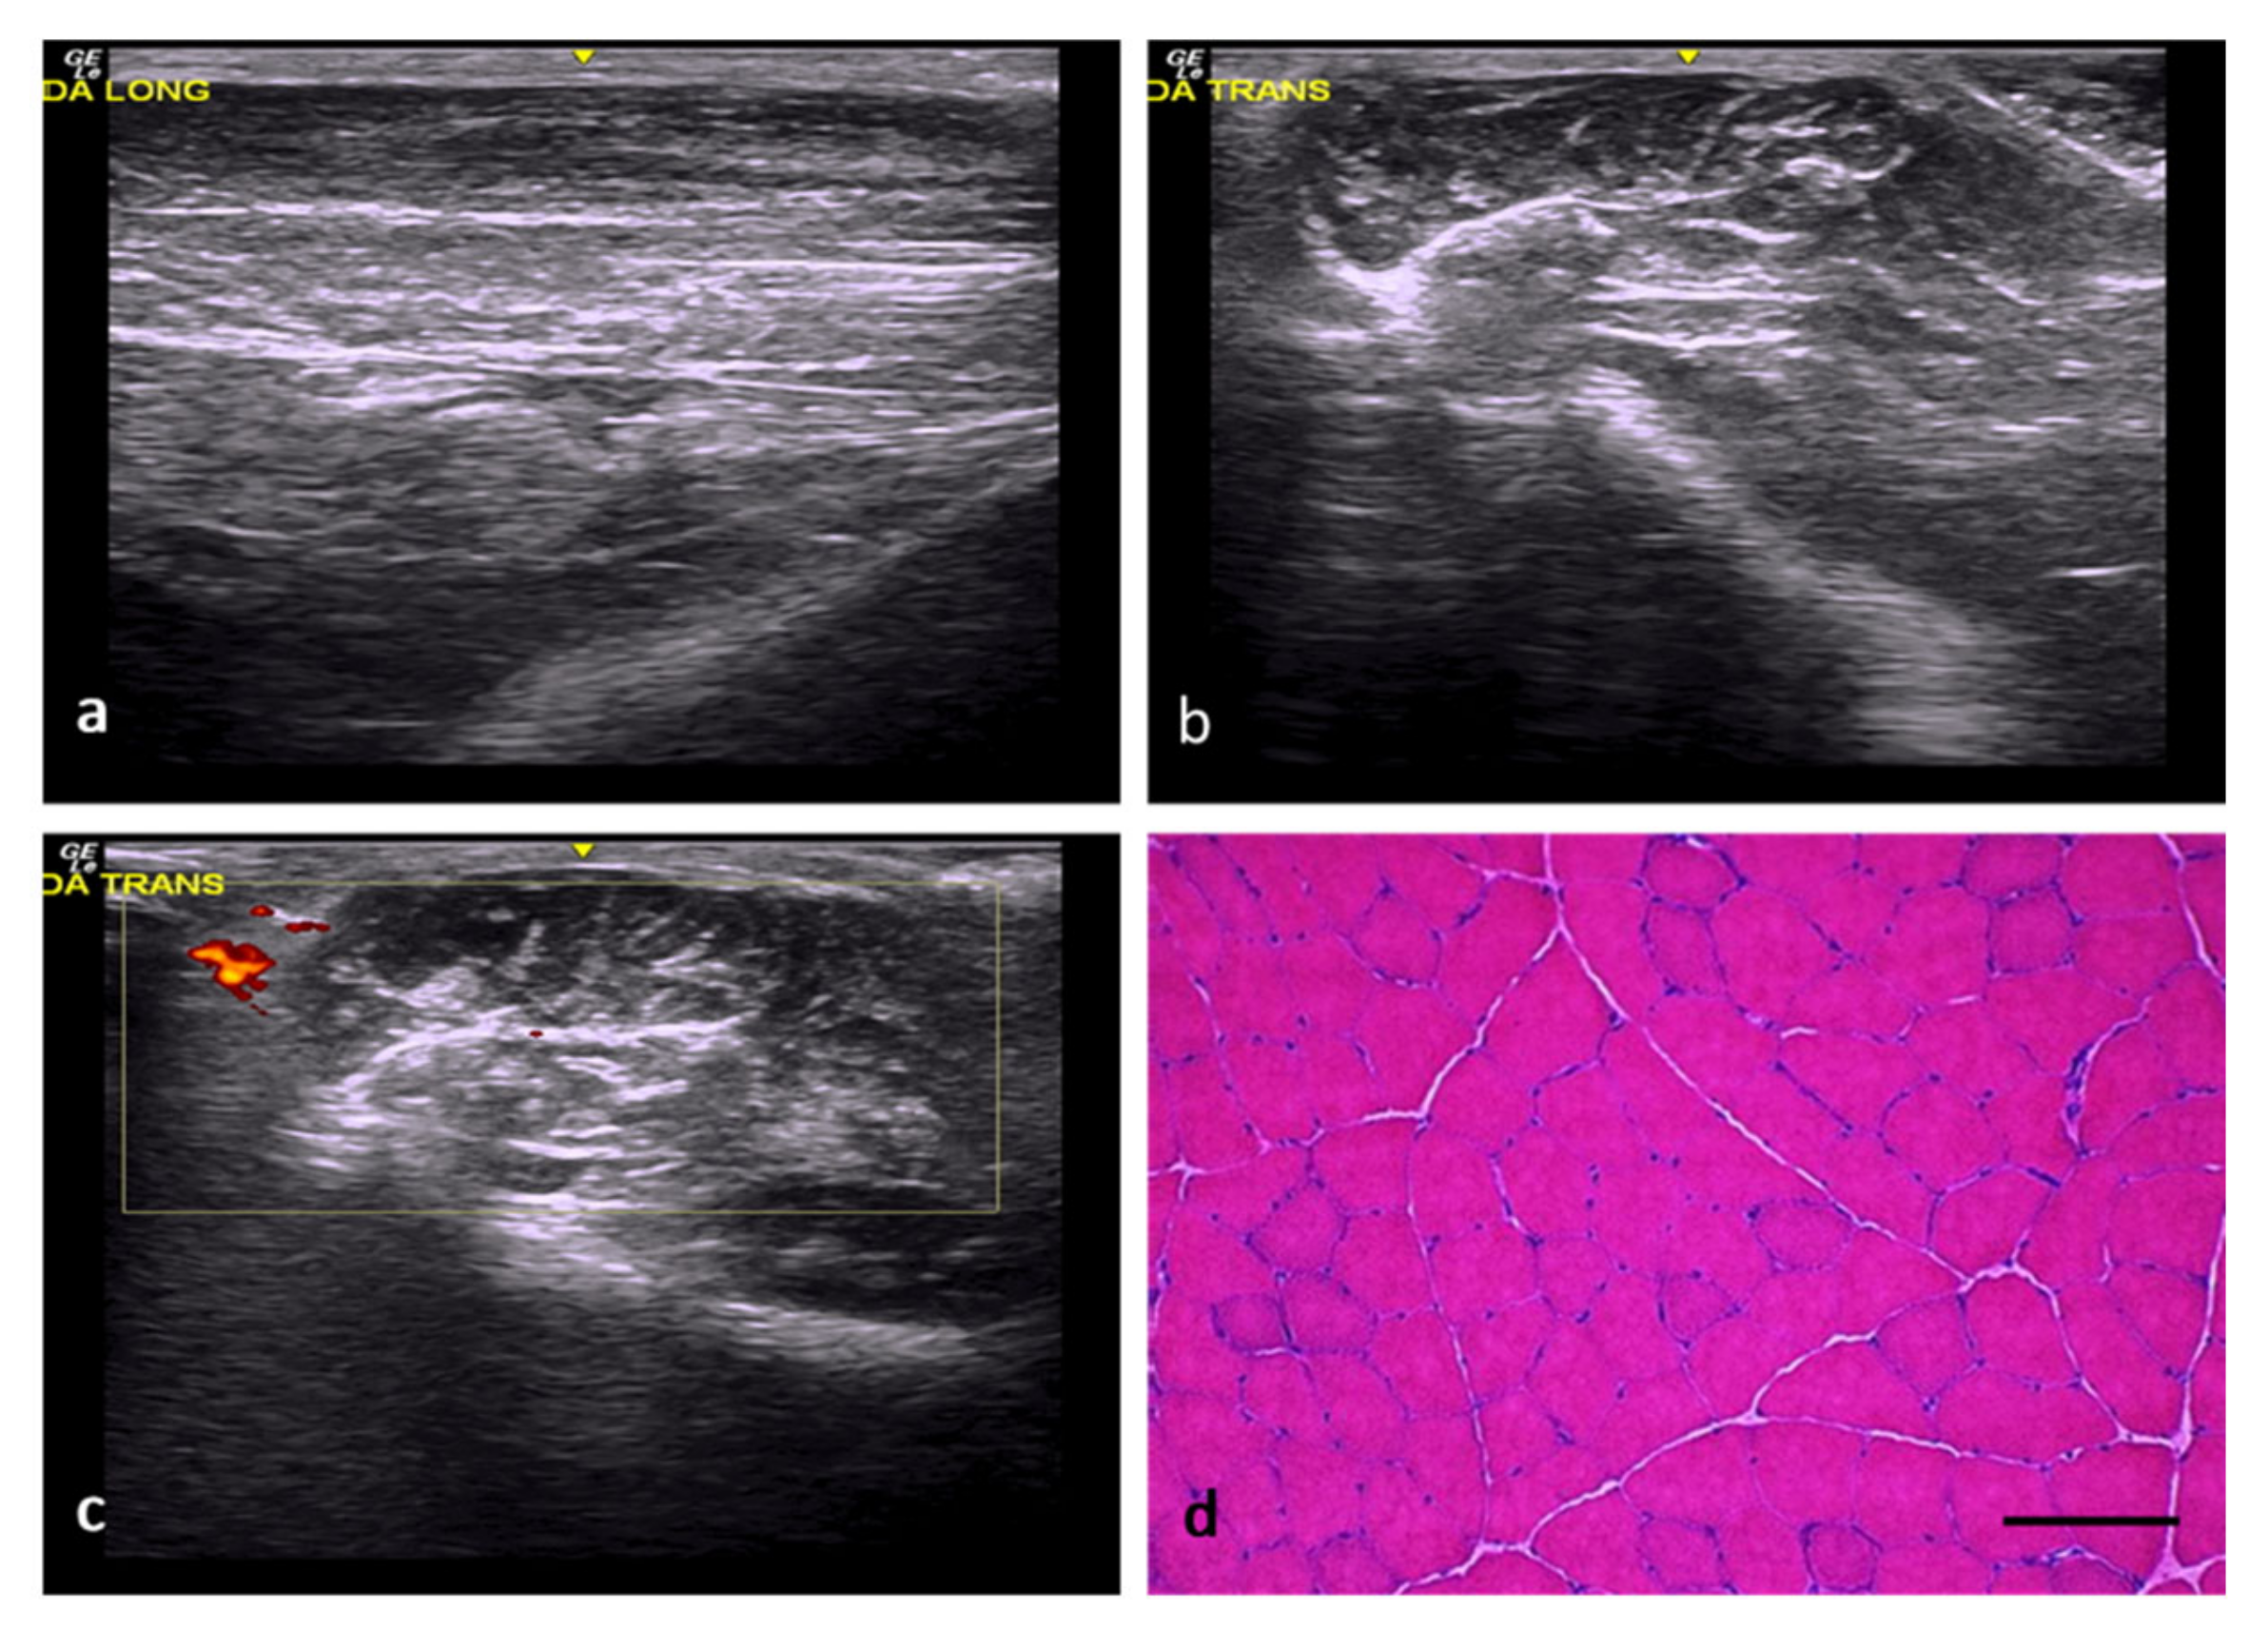

In the rats of the normal control (NC) group, the muscles exhibited a normal echogenicity and echostructure formed by hypoechoic muscle fibers interspersed with fibrous septa and echogenic fasciae (Figure 1a–c). Along the longitudinal axis, the normal echostructure of the muscle comprised a background of relatively hypoechoic bands corresponding to the muscle fibers interspersed with numerous linear hyperechoic bands corresponding to the fibroadipose septa (perimysium). The same hypoechoic background (muscle fibers) was also observed along the transverse axis, in addition to countless interspersed and disorganized dots and small hyperechoic lines (perimysium) that generated a “starry sky” appearance. The epimysium was identified along both axes, together with a well-defined hyperechoic linear band enveloping the predominantly hypoechoic muscle. Doppler imaging under normal conditions allowed the identification of small, isolated vessels in the connective tissue surrounding the muscle fibers. From a histological point of view, these muscle fibers had rounded or polygonal profiles, peripheral nuclei, and were grouped in bundles (Figure 1d).

Figure 1.

NC group. (a) Normal muscle echostructure along the longitudinal axis, comprising a hypoechoic background with numerous hyperechoic lines corresponding to the perimysial septa. (b) Normal muscle echostructure along the transverse axis, with a predominantly hypoechoic background with small, interspersed hyperechoic lines and dots corresponding to the perimysium. (c) Transverse section assessed by power Doppler imaging, with images of scarce vascularization in the surrounding connective tissue. (d) Transverse section representative of the muscle histology. H-E. Size scale: 100 µm.